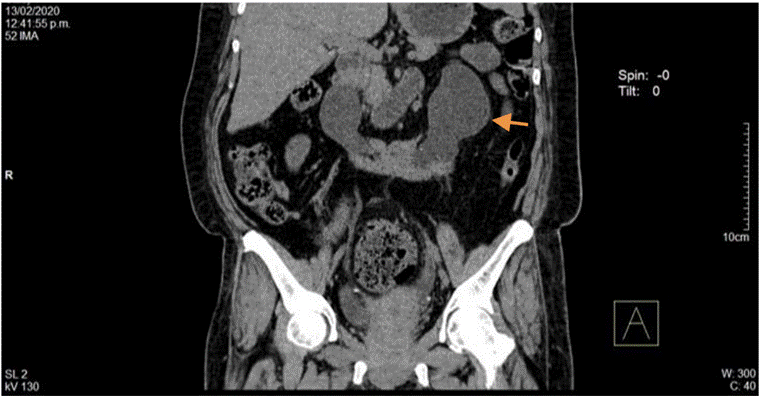

En el UROTAC de control (Figura 7) no se evidenció gas a nivel de parénquima renal.

El urocultivo fue positivo para E. coli sensible a piperacilina tazobactam; los hemocultivos fueron negativos y la diarrea se resolvió (tenía coprológico normal). Tras 15 días de hospitalización y al considerar adecuada respuesta al manejo instaurado, se planteó completar manejo antibiótico en extensión hospitalaria por 21 días con mejoría clínica en el seguimiento ambulatorio.